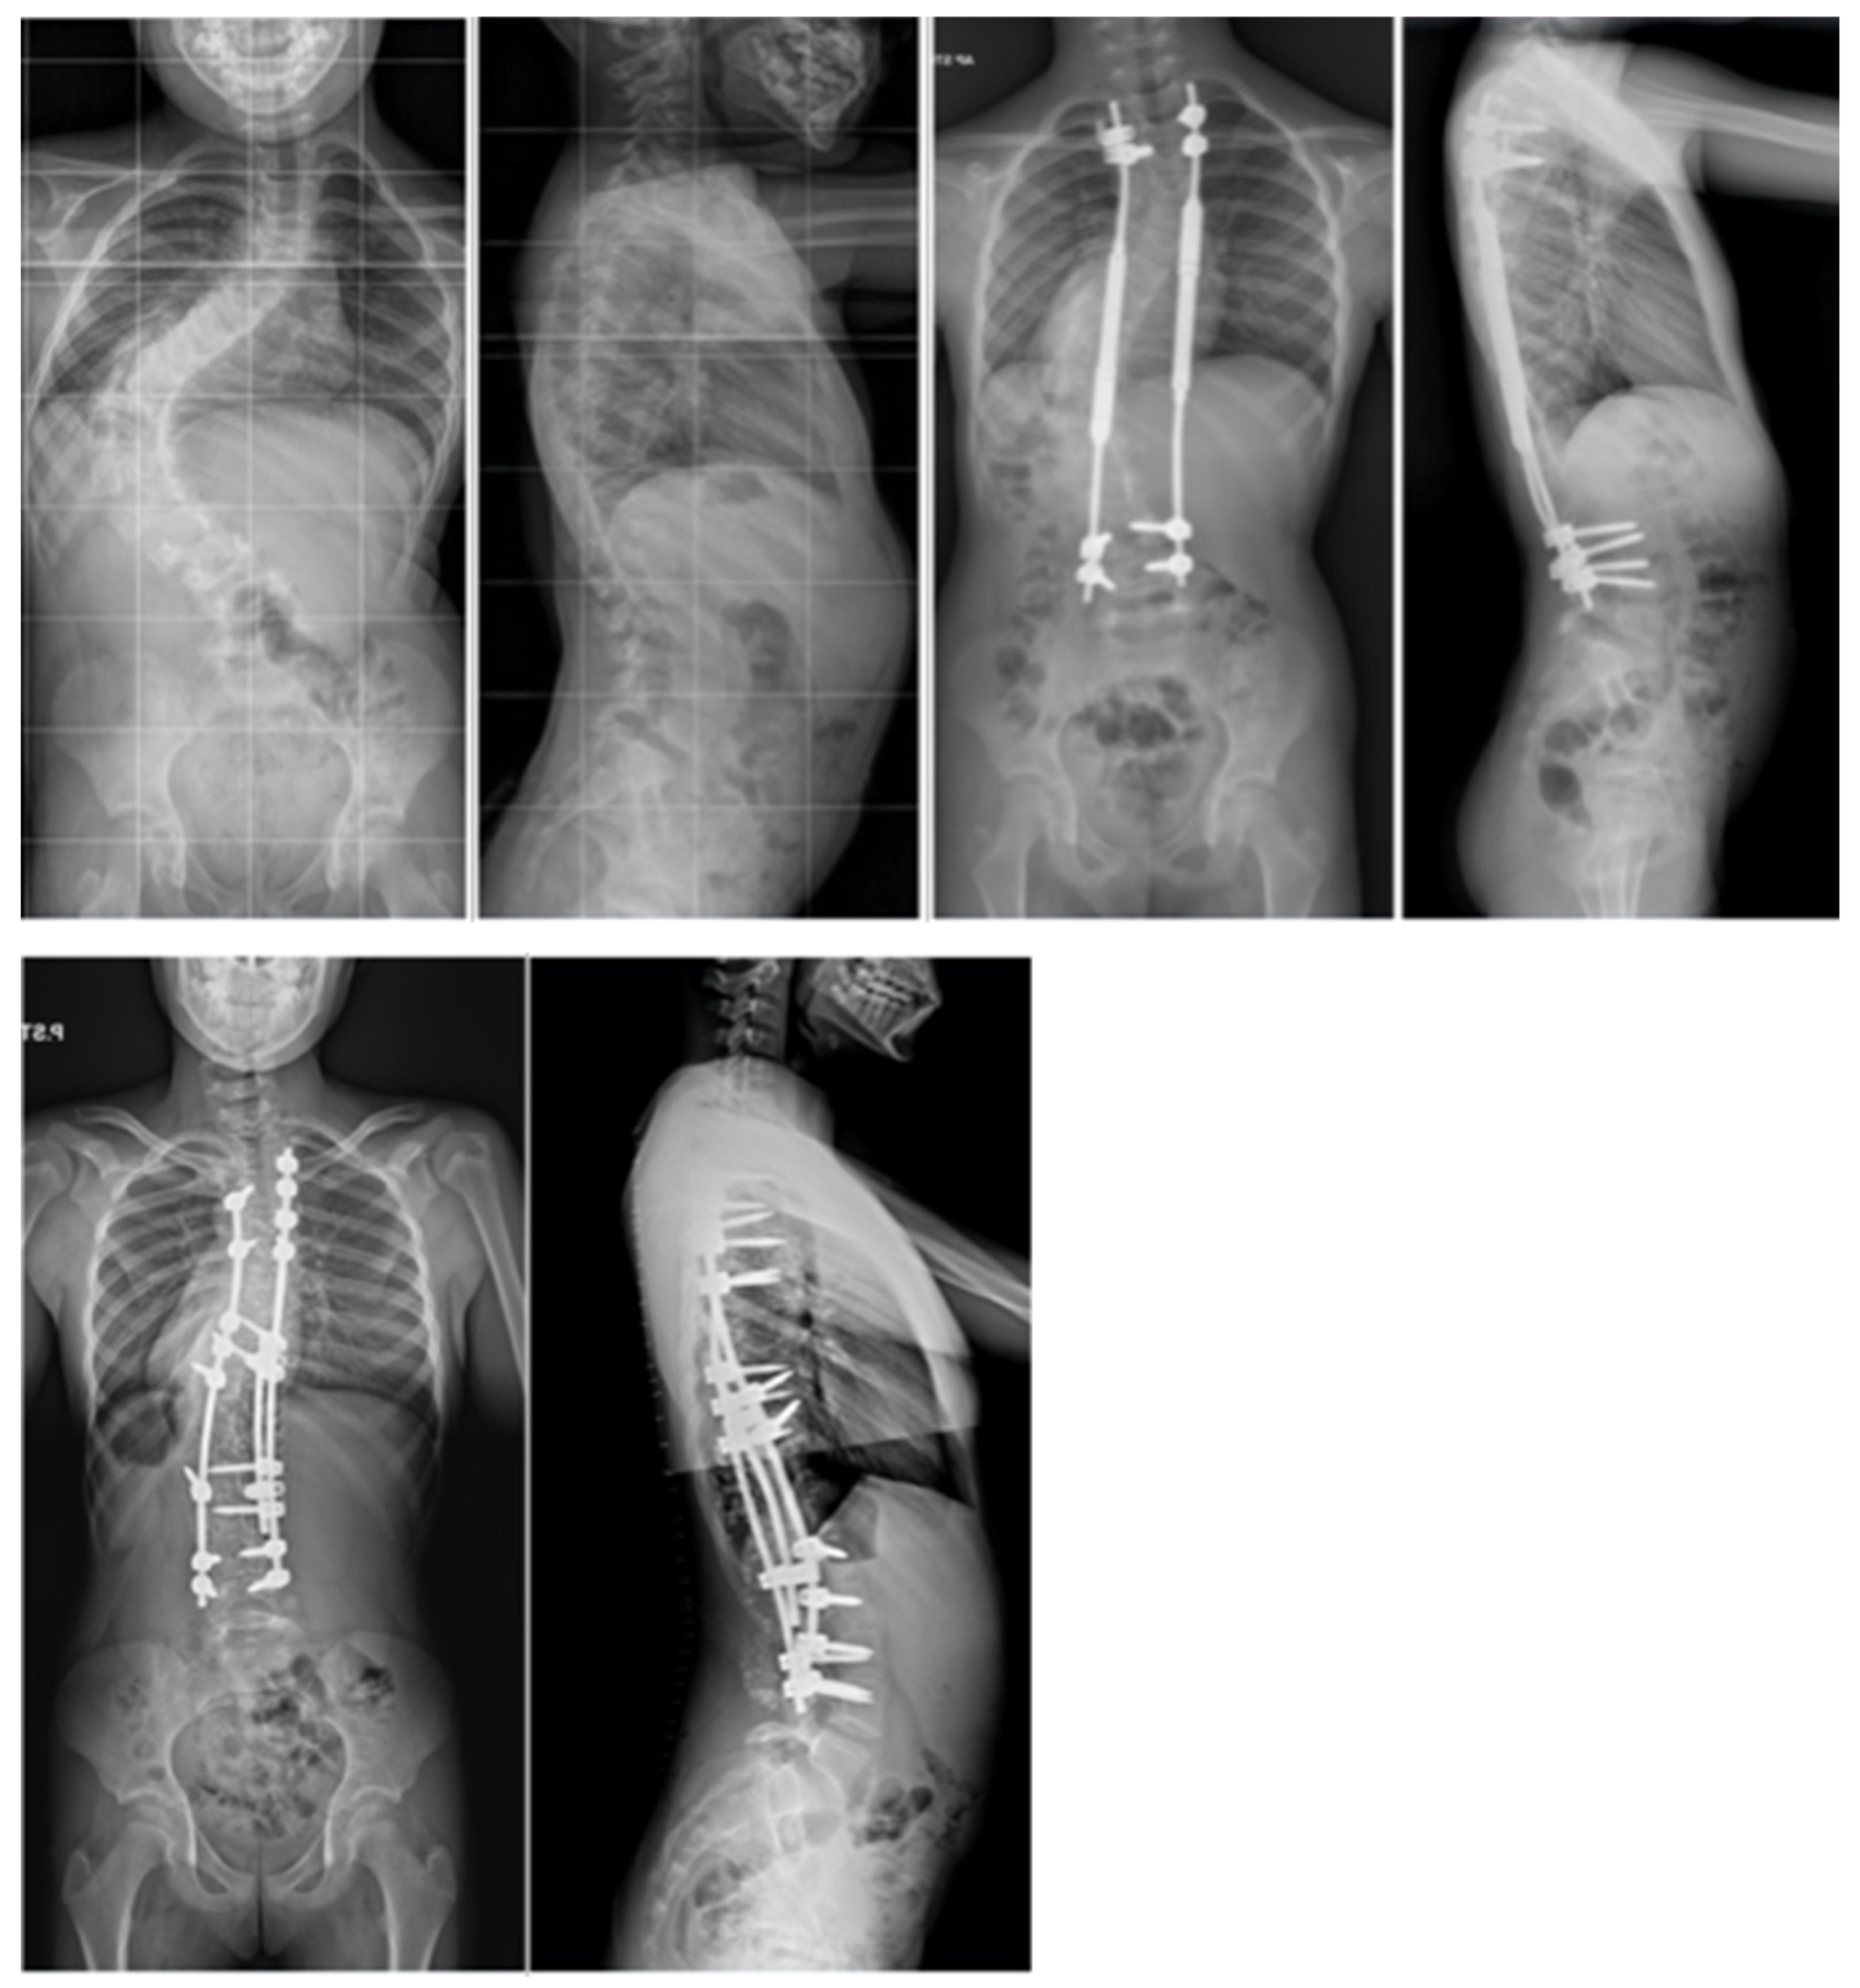

- Buchowski, J.M.; Skaggs, D.L.; Sponseller, P.D. Temporary internal distraction as an aid to correction of severe scoliosis: Surgical technique. J. Bone Joint Surg. Am. 2007, 89, 297–309. [Google Scholar] [CrossRef] [PubMed]

- Grabala, P.; Galgano, M.A.; Grabala, M.; Buchowski, J.M. Radiological and Pulmonary Results of Surgical Treatment of Severe Idiopathic Scoliosis Using Preoperative Halo Gravity Traction Compared with Less Invasive Temporary Internal Distraction in Staged Surgery in Adolescents. J. Clin. Med. 2024, 13, 2875. [Google Scholar] [CrossRef] [PubMed]

- Buchowski, J.M.; Bhatnagar, R.; Skaggs, D.L.; Sponseller, P.D. Temporary internal distraction as an aid to correction of severe scoliosis. J. Bone Joint Surg. Am. 2006, 88, 2035–2041. [Google Scholar] [CrossRef] [PubMed]

- Skaggs, D.L.; Lee, C.; Myung, K.S. Neuromonitoring Changes Are Common and Reversible With Temporary Internal Distraction for Severe Scoliosis. Spine Deform. 2014, 2, 61–69. [Google Scholar] [CrossRef]

- Hu, H.M.; Hui, H.; Zhang, H.P.; Huang, D.G.; Liu, Z.K.; Zhao, Y.T.; He, S.M.; Zhang, X.F.; He, B.R.; Hao, D.J. The impact of posterior temporary internal distraction on stepwise corrective surgery for extremely severe and rigid scoliosis greater than 130°. Eur. Spine J. 2016, 25, 557–568. [Google Scholar] [CrossRef]

- Badin, D.; Skaggs, D.L.; Sponseller, P.D. Temporary Internal Distraction for Severe Scoliosis. JBJS Essent. Surg. Tech. 2022, 12, e22.00006. [Google Scholar] [CrossRef]